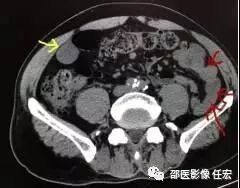

如图3:这是一个未按规范做的患者,红色箭头可见未被水充盈而聚集的小肠,这时候就很容易漏了这里的病灶。而黄色箭头的是被水充盈的一小部分肠管,小肠壁是薄的。